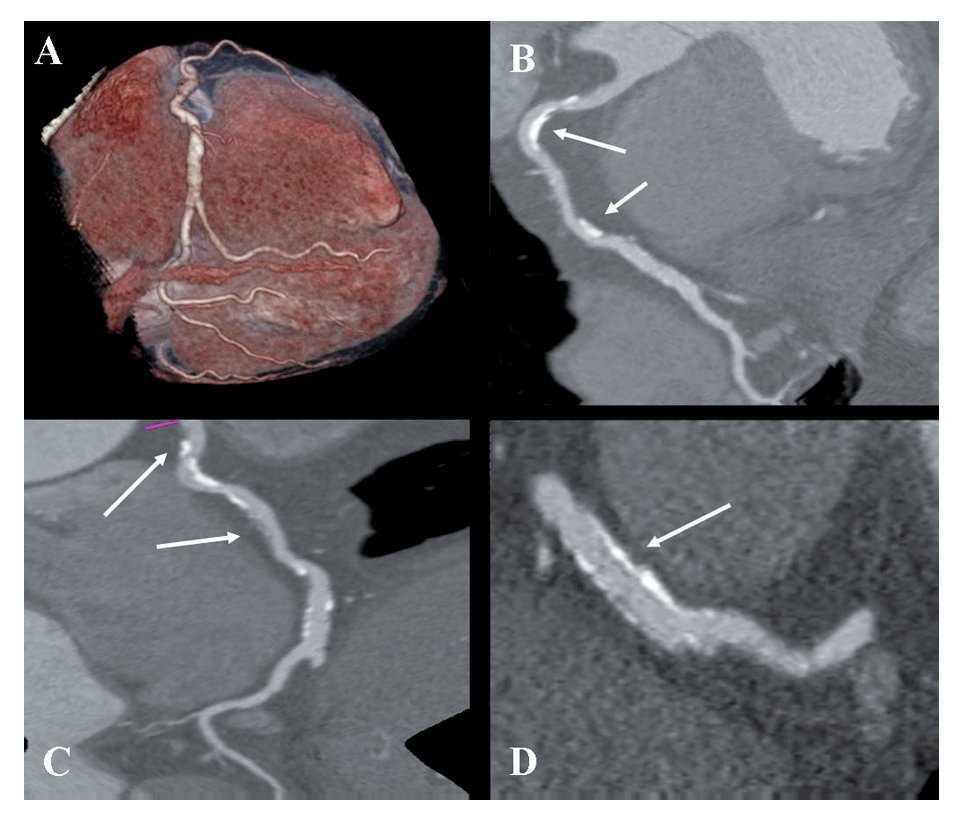

Figure 1.Retrospective ECG-gated dual-energy CT scan reconstruction; merging 70% of the 140-kV spectrum and 30% of the 100-kV spectrum shown as volume rendering of the right coronary artery (RCA) (A); curved multiplanar reconstruction revealing the presence of two-highly calcified plaques in the RCA (arrows in B and C), and a longitudinal multiplanar image at the stent level in the RCA, processed with a s edge-enhancing kernel (B46f) to optimize the visualization of the stent lumen which demonstrated a mild neointimal hyperplasia (arrows in D).

Figure 1 coronary CT angiogram images revealed right dominant circulation with normal left main coronary artery and non-significant stenosis in the left anterior descending and circumflex arteries territory. Analysis of the RCA showed two high-density calcified plaques with an intermediate stenosis in the middle segment of the RCA (Figures 1B and 1C). Multiplanar images with a special post-processing B46f reconstruction filter showed a patent stent with a very mild neointimal hyperplasia (thin dark line inside the stent lumen) (Figure 1D). Figure 2 coronary CT angiogram images demonstrated a subendocardial perfusion defect in the right coronary territory, within the inferior and inferolateral wall of the left ventricle (area that appears as a black thick line at the subendocardial region) (Figures 2B, 2C and 2D).